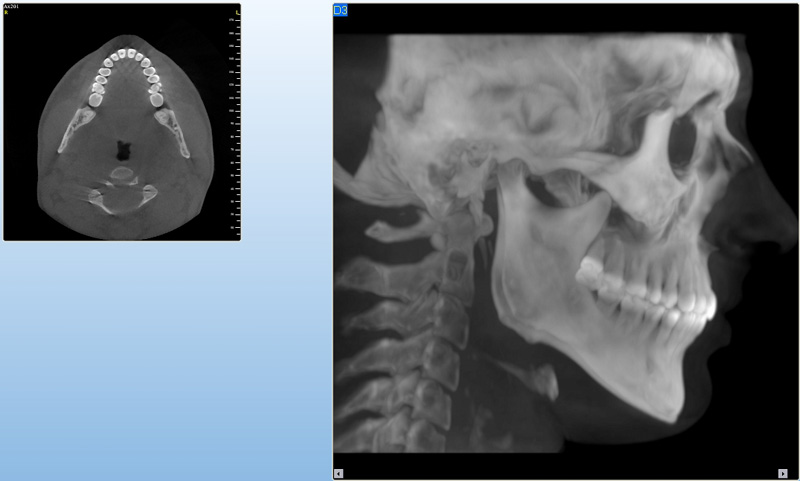

Jedná se o nejnovějším přístroj ze skupiny dentálních hybridních CBCT (3D) + 2D (pan i ceph) systémů. Přístroj umožňuje na základě jediného snímkování vytvořit všechny typy RTG zobrazení, které jsou pro lékaře potřebné.

Používaná technologii tzv. „kuželového paprsku“ a speciální senzory pro minimální zátěž při snímkování pacienta

(o více jak 80% nižší dávka proti klasickému CT).

Pomocí tohoto přístroje je možné zjisti skutečnou situaci v čelistních kostech pacienta tedy množství kosti - můžeme změřit skutečnou šířku i výšku kosti, i kvalitu kosti (hustotu) v místě uvažované implantace. 3D (tříprostorové) zobrazení umožňuje

zvýšit prostorovou představu operatéra ještě před vlastní operací a zároveň pacientovi lépe objasnit a ukázat oblast plánovaného zavedení implantátu.

Lékař si vytvoří všechny typy zobrazení potřebných pro naplánování – tedy 2D snímky (panoramatický), příčné řezy i 3D model.

Vidí zde i důležité anatomické útvary – čelistní dutinu, průběh nervu atd. Po proměření množství kosti – šířky i výšky vybere z databáze vhodný typ implantátu a umístí ho do požadované lokality.